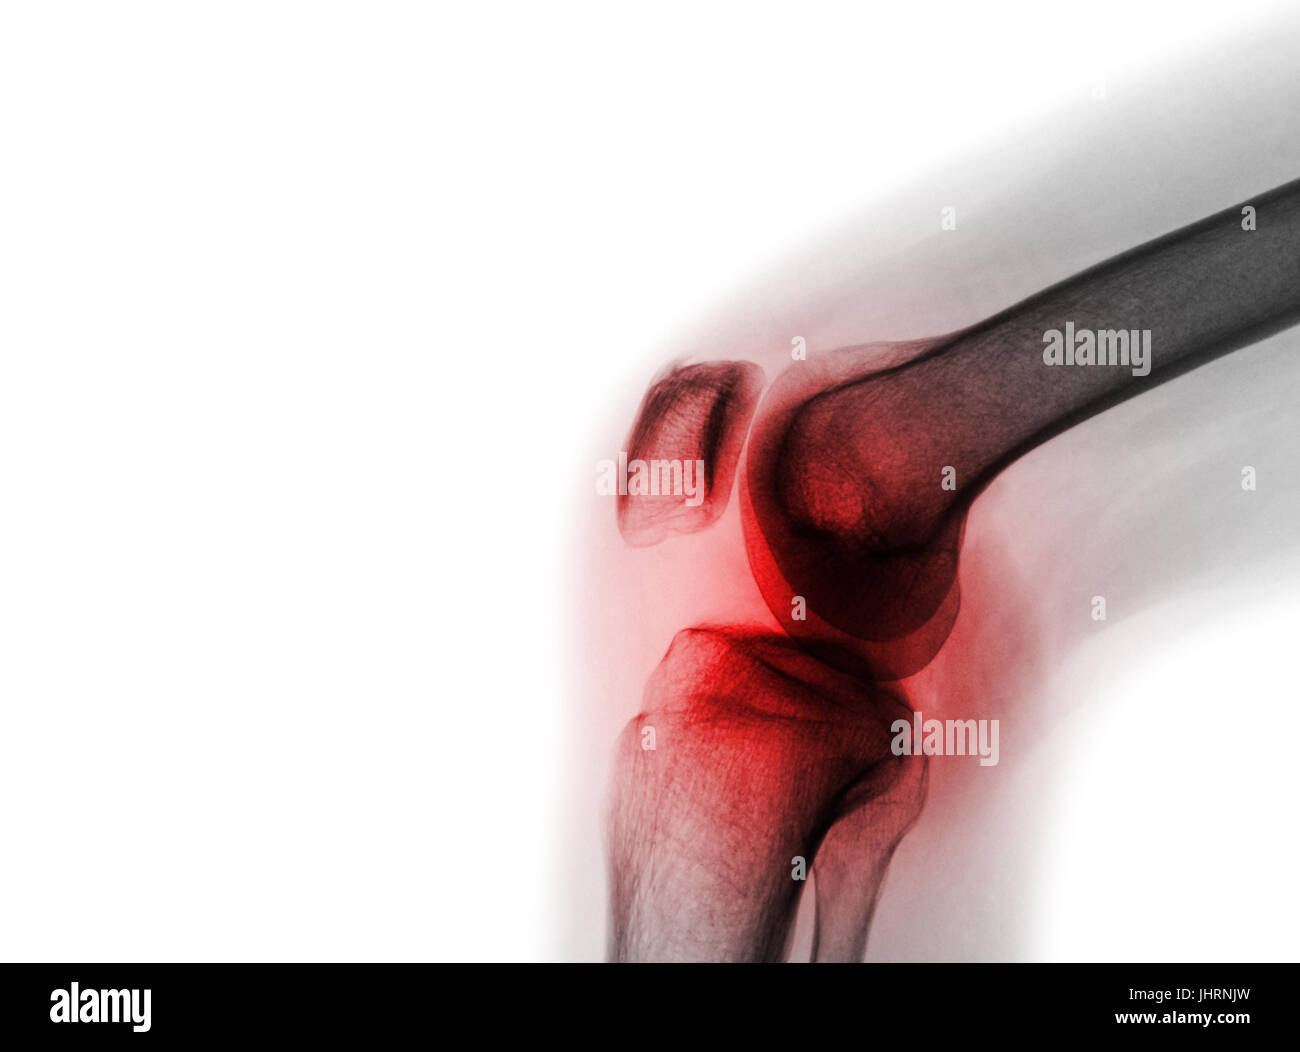

Film x-ray de la normale du genou et la zone vide du côté gauche . Banque D'Imageshttps://www.alamyimages.fr/image-license-details/?v=1https://www.alamyimages.fr/photo-image-film-x-ray-de-la-normale-du-genou-et-la-zone-vide-du-cote-gauche-148653981.html

Film x-ray de la normale du genou et la zone vide du côté gauche . Banque D'Imageshttps://www.alamyimages.fr/image-license-details/?v=1https://www.alamyimages.fr/photo-image-film-x-ray-de-la-normale-du-genou-et-la-zone-vide-du-cote-gauche-148653981.htmlRFJHRNJN–Film x-ray de la normale du genou et la zone vide du côté gauche .

Film x-ray de la normale du genou et la zone vide du côté gauche . Banque D'Imageshttps://www.alamyimages.fr/image-license-details/?v=1https://www.alamyimages.fr/photo-image-film-x-ray-de-la-normale-du-genou-et-la-zone-vide-du-cote-gauche-148653983.html

Film x-ray de la normale du genou et la zone vide du côté gauche . Banque D'Imageshttps://www.alamyimages.fr/image-license-details/?v=1https://www.alamyimages.fr/photo-image-film-x-ray-de-la-normale-du-genou-et-la-zone-vide-du-cote-gauche-148653983.htmlRFJHRNJR–Film x-ray de la normale du genou et la zone vide du côté gauche .

Film x-ray articulation du genou avec l'arthrite ( la goutte, l'arthrite rhumatoïde, l'arthrite septique , l'arthrose du genou ) et la zone vide du côté gauche Banque D'Imageshttps://www.alamyimages.fr/image-license-details/?v=1https://www.alamyimages.fr/photo-image-film-x-ray-articulation-du-genou-avec-l-arthrite-la-goutte-l-arthrite-rhumatoide-l-arthrite-septique-l-arthrose-du-genou-et-la-zone-vide-du-cote-gauche-148653982.html

Film x-ray articulation du genou avec l'arthrite ( la goutte, l'arthrite rhumatoïde, l'arthrite septique , l'arthrose du genou ) et la zone vide du côté gauche Banque D'Imageshttps://www.alamyimages.fr/image-license-details/?v=1https://www.alamyimages.fr/photo-image-film-x-ray-articulation-du-genou-avec-l-arthrite-la-goutte-l-arthrite-rhumatoide-l-arthrite-septique-l-arthrose-du-genou-et-la-zone-vide-du-cote-gauche-148653982.htmlRFJHRNJP–Film x-ray articulation du genou avec l'arthrite ( la goutte, l'arthrite rhumatoïde, l'arthrite septique , l'arthrose du genou ) et la zone vide du côté gauche

Film x-ray articulation du genou avec l'arthrite ( la goutte, l'arthrite rhumatoïde, l'arthrite septique , l'arthrose du genou ) et la zone vide du côté gauche Banque D'Imageshttps://www.alamyimages.fr/image-license-details/?v=1https://www.alamyimages.fr/photo-image-film-x-ray-articulation-du-genou-avec-l-arthrite-la-goutte-l-arthrite-rhumatoide-l-arthrite-septique-l-arthrose-du-genou-et-la-zone-vide-du-cote-gauche-148653985.html

Film x-ray articulation du genou avec l'arthrite ( la goutte, l'arthrite rhumatoïde, l'arthrite septique , l'arthrose du genou ) et la zone vide du côté gauche Banque D'Imageshttps://www.alamyimages.fr/image-license-details/?v=1https://www.alamyimages.fr/photo-image-film-x-ray-articulation-du-genou-avec-l-arthrite-la-goutte-l-arthrite-rhumatoide-l-arthrite-septique-l-arthrose-du-genou-et-la-zone-vide-du-cote-gauche-148653985.htmlRFJHRNJW–Film x-ray articulation du genou avec l'arthrite ( la goutte, l'arthrite rhumatoïde, l'arthrite septique , l'arthrose du genou ) et la zone vide du côté gauche